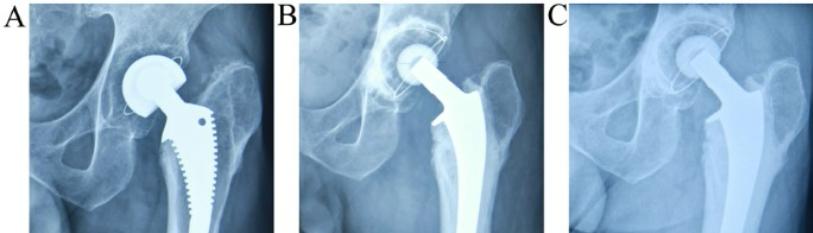

Figure 1: AT admission shows displace neck of femur fracture with 1st generation cephalomedullay nail.

Figure 2: post op day 1 x ray shows hemiarthroplasty with prophylaxis cerclage wires.

Figure 3: post op 1 year shows stable hemiarthroplasty.